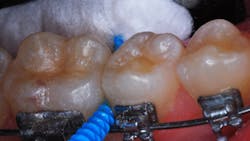

Typical dental soft picks are dipped and coated with SDF solution (figure 1). A bitewing film from May 16, 2019, shows radiolucent changes on the mesial surfaces of both permanent first molars (figure 2, top left). The first dental pick coated with SDF was used at this appointment.

The patient returned for a routine recall appointment on April 6, 2021, wearing fixed orthodontic hardware. A bitewing radiograph was taken (figure 2, top right). The site was cleared with floss, and a new pick soaked with SDF was inserted (figure 3). A small applicator was used to paint sluiceways to enhance the flow of SDF. The pick was slid in and out of the interproximal surfaces a few times (figure 4). The treatment site was immersed in 5% fluoride varnish (figure 5).